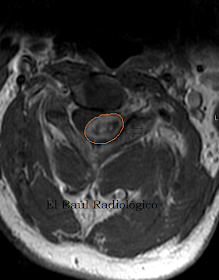

FIGURA 1-D) Imagen axial FSE-T1 Gadolinio. El schwannoma se realza de forma intensa después de administrar contraste.